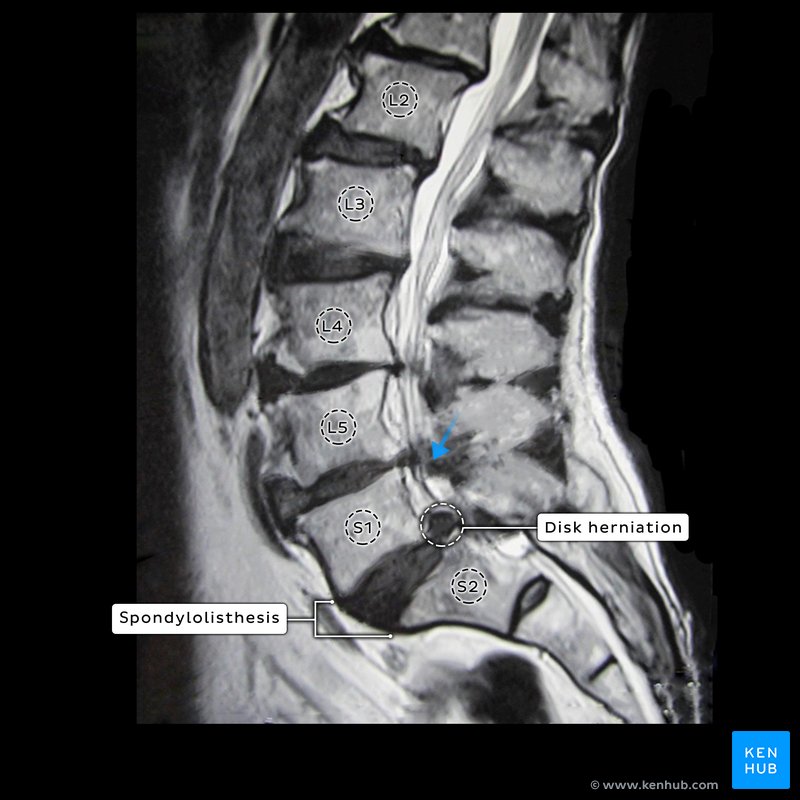

Plain radiographs of the lumbosacral spine showed spondylolisthesis of S1-S2 (Figures 1--3).

MRI and CT scans revealed lumbarization of S1 with spondylolisthesis of S1 over S2, facetal hypertrophy at L5-S1, and canal stenosis at S1-S2 and disk herniation at that level (Figures 2&3). Hematological analysis was negative.

The detrusor muscle is innervated by parasympathetic nerves. These fibers originate as pelvic splanchnic nerves, pass through the inferior hypogastric plexus, reach the bladder wall and synapse within the wall with postganglionic fibers, which, in turn, stimulate muscle contraction. Although sympathetic fibers also reach the bladder wall (from L1 and L2 segments via hypogastric plexus), these nerves probably are mainly vasomotor (in males however they supply the distinct muscle at the bladder neck as described above). In the patient, in this case, the compression of the sacral nerves due to the spondylolisthesis (Figure 3) affected the parasympathetic fibers in spinal nerves S2-4 resulting in a flaccid bladder that retained urine.

The anal wink, anal reflex, perineal reflex, or anocutaneous reflex is the reflexive contraction (puckering) of the external anal sphincter upon stroking of the skin around the anus. The stimulus is detected by the nociceptors in the skin that are supplied by the inferior rectal nerves (branches of the pudendal nerve); their reflex response is mediated via spinal cord sacral segments S2-S4. The absence of this reflex indicates that there is an interruption of the reflex arc, or damage to the spinal cord. In the case of this patient, the S2-S4 spinal nerves were being compressed as evidenced by the absence of this reflex as well as the urine retention (Figure 3).